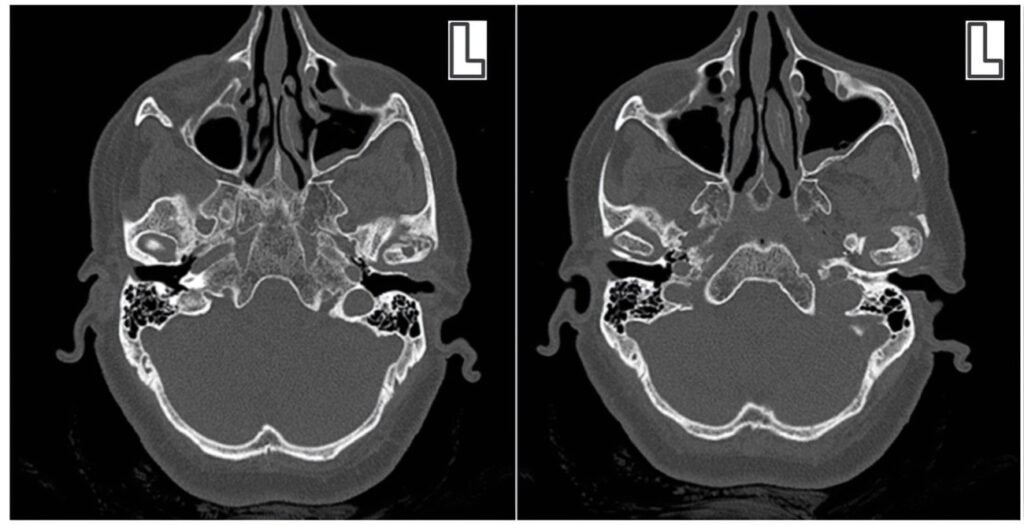

Zebris vs. Static Imaging (X-rays, CBCT):

- Static imaging shows anatomical structures but not functional movement

- Zebris captures dynamic function but not detailed anatomy

- Combined approach often provides the most comprehensive diagnosis